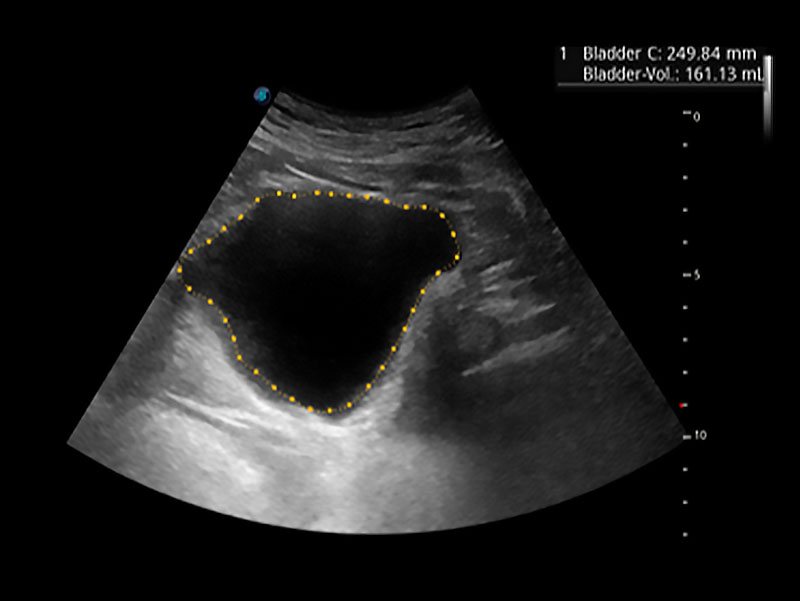

一鍵自動(dòng)識(shí)別膀胱壁及自動(dòng)測(cè)量膀胱容積,不受膀胱形狀和大小的限制,幫助醫(yī)生快速精準(zhǔn)獲得測(cè)量的數(shù)據(jù)。